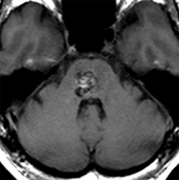

腦干海綿狀血管瘤的特征和癥狀

腦干海綿狀血管瘤的特征和癥狀,和其他部位的海綿狀血管瘤一樣,無癥狀被發(fā)現的情況也很多。無癥狀的情況下可以觀察。腦干部也有順利區(qū),一部分切開也不容易出癥狀的部分。使用兩點法...